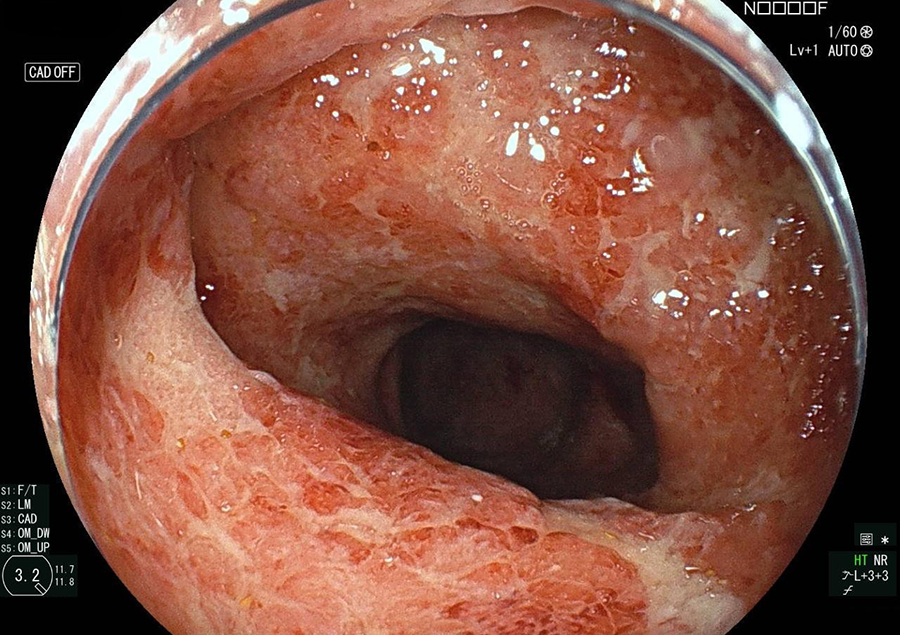

検査の様子

④検査

ベッドへご案内し、検査着に着替えていただきます。準備が整いましたら、順番に検査室へご案内します。

鎮静剤を静脈注射し、心身ともに緊張を和らげてから検査を開始します。